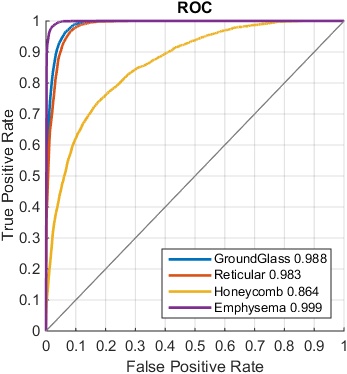

The classification results are shown using the ROC curves in Fig. 5, and F-scores are presented in Table 3 and Table 4 while setting the pathology presence thresholds to be and , respectively. The overall F-score is calculated based on the multi-label classification evaluation mentioned in Sec. 4.2. We obtain good results using the setting of but the quantitative results by setting are further improved, indicating that our algorithm may be robust to detect smaller ILD patterns and can tolerate some pixel-level annotation errors in LTRC. In our setting, pixel-level ILD annotations are not essentially required. Therefore the medical experts can simply provide the holistic CT slice-level labels on any lung CT image to indicate if there are ILD presences worth reporting, without annotating particular ILD image ROIs. It would considerably save the labeling time for experts to annotate the training dataset.

4.4 Results on Multi-label Regression CNN

We can treat the continuously-valued output vector, either in the form of pixel number counts or binary presence status, as the “classification confidence scores” after the multi-label regression CNN processes an input CT image. These regressed confidence scores can be compared against the ground truth binary ILD labels obtained by thresholding on as in Sec. 4.3. In this manner, ILD classification receiver operating characteristic (ROC) curves are generated. Our experiments are conducted via the three label converting functions or plots in Fig. 3. Two variations of CNN regression outputs to match the ILD occupied pixel numbers per-slice, or the binary ILD presence labels produce similar quantitative ILD classification results. The piecewise linear transformation (Fig. 3 Right) yields slightly inferior results.

The overall performance of multi-label regression CNN when the smooth loss is employed is generally comparable with the multi-label classification CNN (Sec. 4.3). From Table 4 and 3, the smooth regression CNN performs slightly better overall and particularly for the ground glass class, but the multi-label classification CNN outperforms in the categories of reticular, honeycomb, and emphysema with moderate margins.

When constructing the FV-encoded features, , the local convolutional image descriptors are pooled into Gaussian components, producing a dimensionality as high as 16K [21]. We further reduce the FV features to dimensions using PCA. The performance is empirically found to be insensitive to the number of Gaussian kernels and the dimensions after PCA. We compare the ILD classification performance with FV encoding, on the features pooled from different CNN layers, using area-under-the-curve (AUC) values (in Table 5) and F-scores (in Table 6), respectively.